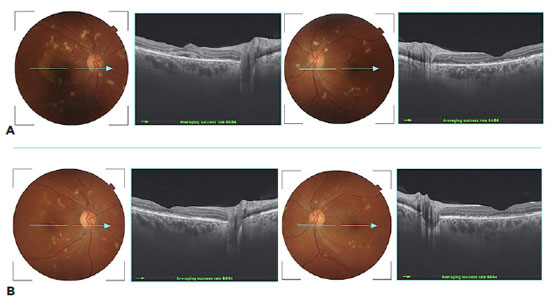

A 33-year-old woman presented with sudden bilateral visual loss in both eyes (OU) over three weeks. She had a three-year history of uncontrolled systemic arterial hypertension. Best-corrected visual acuity (BCVA) was 20/400 in the right eye (OD) and 20/200 in the left eye (OS). Ocular motility and anterior segment eye examination were unremarkable. Pupils were equal in size with a normal reaction to light. The accommodation was intact. The fundus exam showed bilateral cotton-wool spots, flame-shaped retinal hemorrhages, diffusely narrowed arterioles, mild optic disc edema, and exudative maculopathy (Figure 1A). Swept-source optical coherence tomography (OCT) B-scans showed bilateral macular edema with intraretinal cysts and massive subretinal fluid in OU (Figure 1B). A systemic evaluation revealed a blood pressure of 240/160 mmHg. The patient was hospitalized for hypertension treatment and additional tests. The complete blood count was normal, and serum creatinine was 1.29 mg/dl (reference value (RF): 0.4 to 1.30 mg/dl). Urinalysis demonstrated 4+ proteins, 2+ hemoglobin, and numerous red blood cells (30 per field). Examination of 24-hour urine, in a volume of 1.800 ml, showed proteinuria of 2.592 mg/24 hours (RF <150mg /24 hours). The kidney biopsy showed a granular deposition of IgA and complement (C3) in immunofluorescence staining in an expanded mesangium with foci of segmental and necrotizing proliferative lesions, confirming the immunoglobulin (Ig) A nephropathy. Because of the massive subretinal fluid and severe visual loss, aflibercept 2 mg (0.05 ml) as an intravitreal injection was performed in OU. Three weeks after the procedure, visual acuity (VA) improved markedly to 20/25 in OD and 20/20 in OS. There was also a significant improvement of the exudative maculopathy (Figure 2 A and B). After 10 weeks, there was no sign of sub- or intraretinal fluid, and the BCVA was 20/20 in OU (Figure 2 C and D).